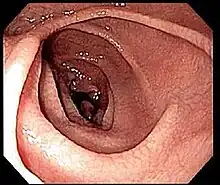

Si la sérologie est positive, une endoscopie de l'intestin grêle avec biopsies sera pratiquée. La fibroscopie peut montrer des anomalies non spécifiques : aspect en mosaïque, plis raréfiés de la muqueuse[56]…

Même en cas de normalité de l'aspect, une confirmation doit être faite par biopsie de la muqueuse duodénale. Elle doit être multiple (4 à 6 échantillons[43]) en raison d'une atteinte pouvant être partielle.

Elle met en évidence une atrophie villositaire associée à une augmentation des lymphocytes intraépithéliaux, une hypertrophie des cryptes et une infiltration plasmolymphocytaire du chorion. Ces lésions sont évaluées selon la classification de Marsh, allant de I (simple augmentation isolée des lymphocytes intraépithéliaux) à IIIc (atrophie villositaire sévère)[53].